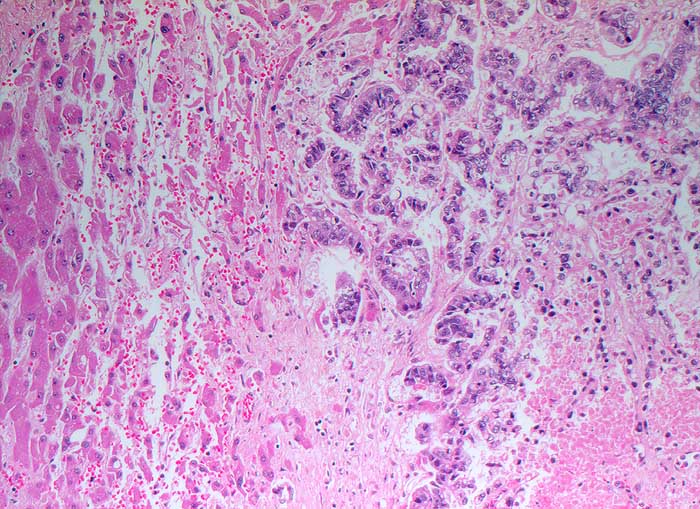

p/ Lebermetastase eines Adenokarzinoms (Magen)

Lebermetastase eines Adenokarzinoms (Magen)

Die Abgrenzung einer Metastase eines wenig differenzierten Adenokarzinoms von einem wenig differenzierten hepatozellulären Karzinom kann schwierig sein. Als wichtige Kriterien für ein HCC gelten monomorphe polygonale Zellen mit zentralen Kernen, Kapillarendothelien und Einschlüsse von Gallepigment. Zur Klärung der Herkunft des Primärtumors können immunzytochemische Untersuchungen weiterhelfen.